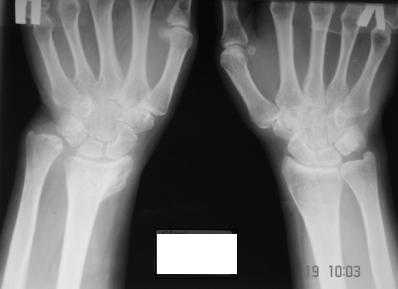

Уважаемые коллеги! Обратилась женщина, 55 лет. Травма 3 месяца назад, лечилась по месту жительства (Рис.1). Косорукость, боли, ограничение движений.

Досняли - рис.2-6. Хотелось-бы услышать мнения об объеме операции. С уважением, Юрий Алексеевич Булахтинглавный травматолог Камчатского Военно-морского госпиталя

u pazientki po nauchnomu ulna abutment/impingment syndrome posle posttraumaticheskogo ukorochenia radiusa

na rengene znachitelnoe ukorochenie radiusa, sustavnaia poverchnost naklonena dorsalno chresmerno , chetko vidno nekongruentnost DRUJ - distalnogo radioulnarnogo sustava ,ulna prosto vtikaetsia v triquetrum .